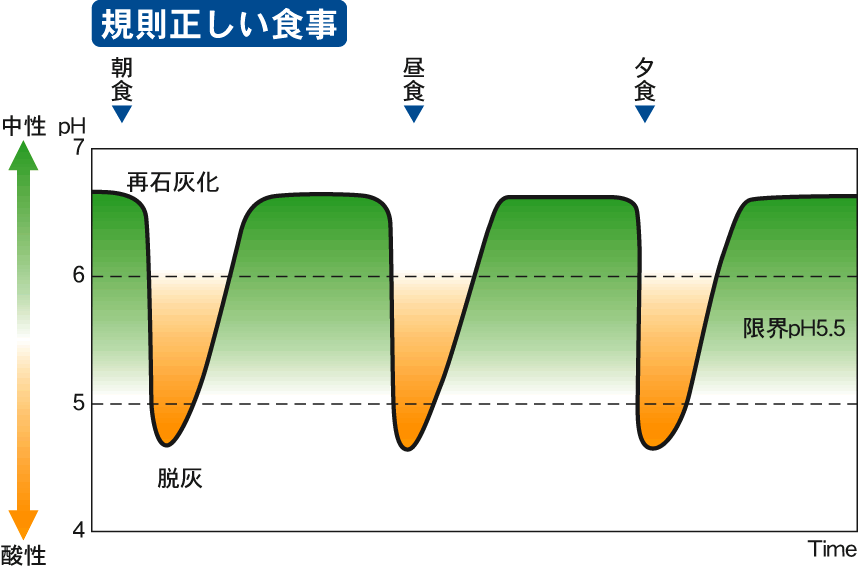

むし歯予防の方法